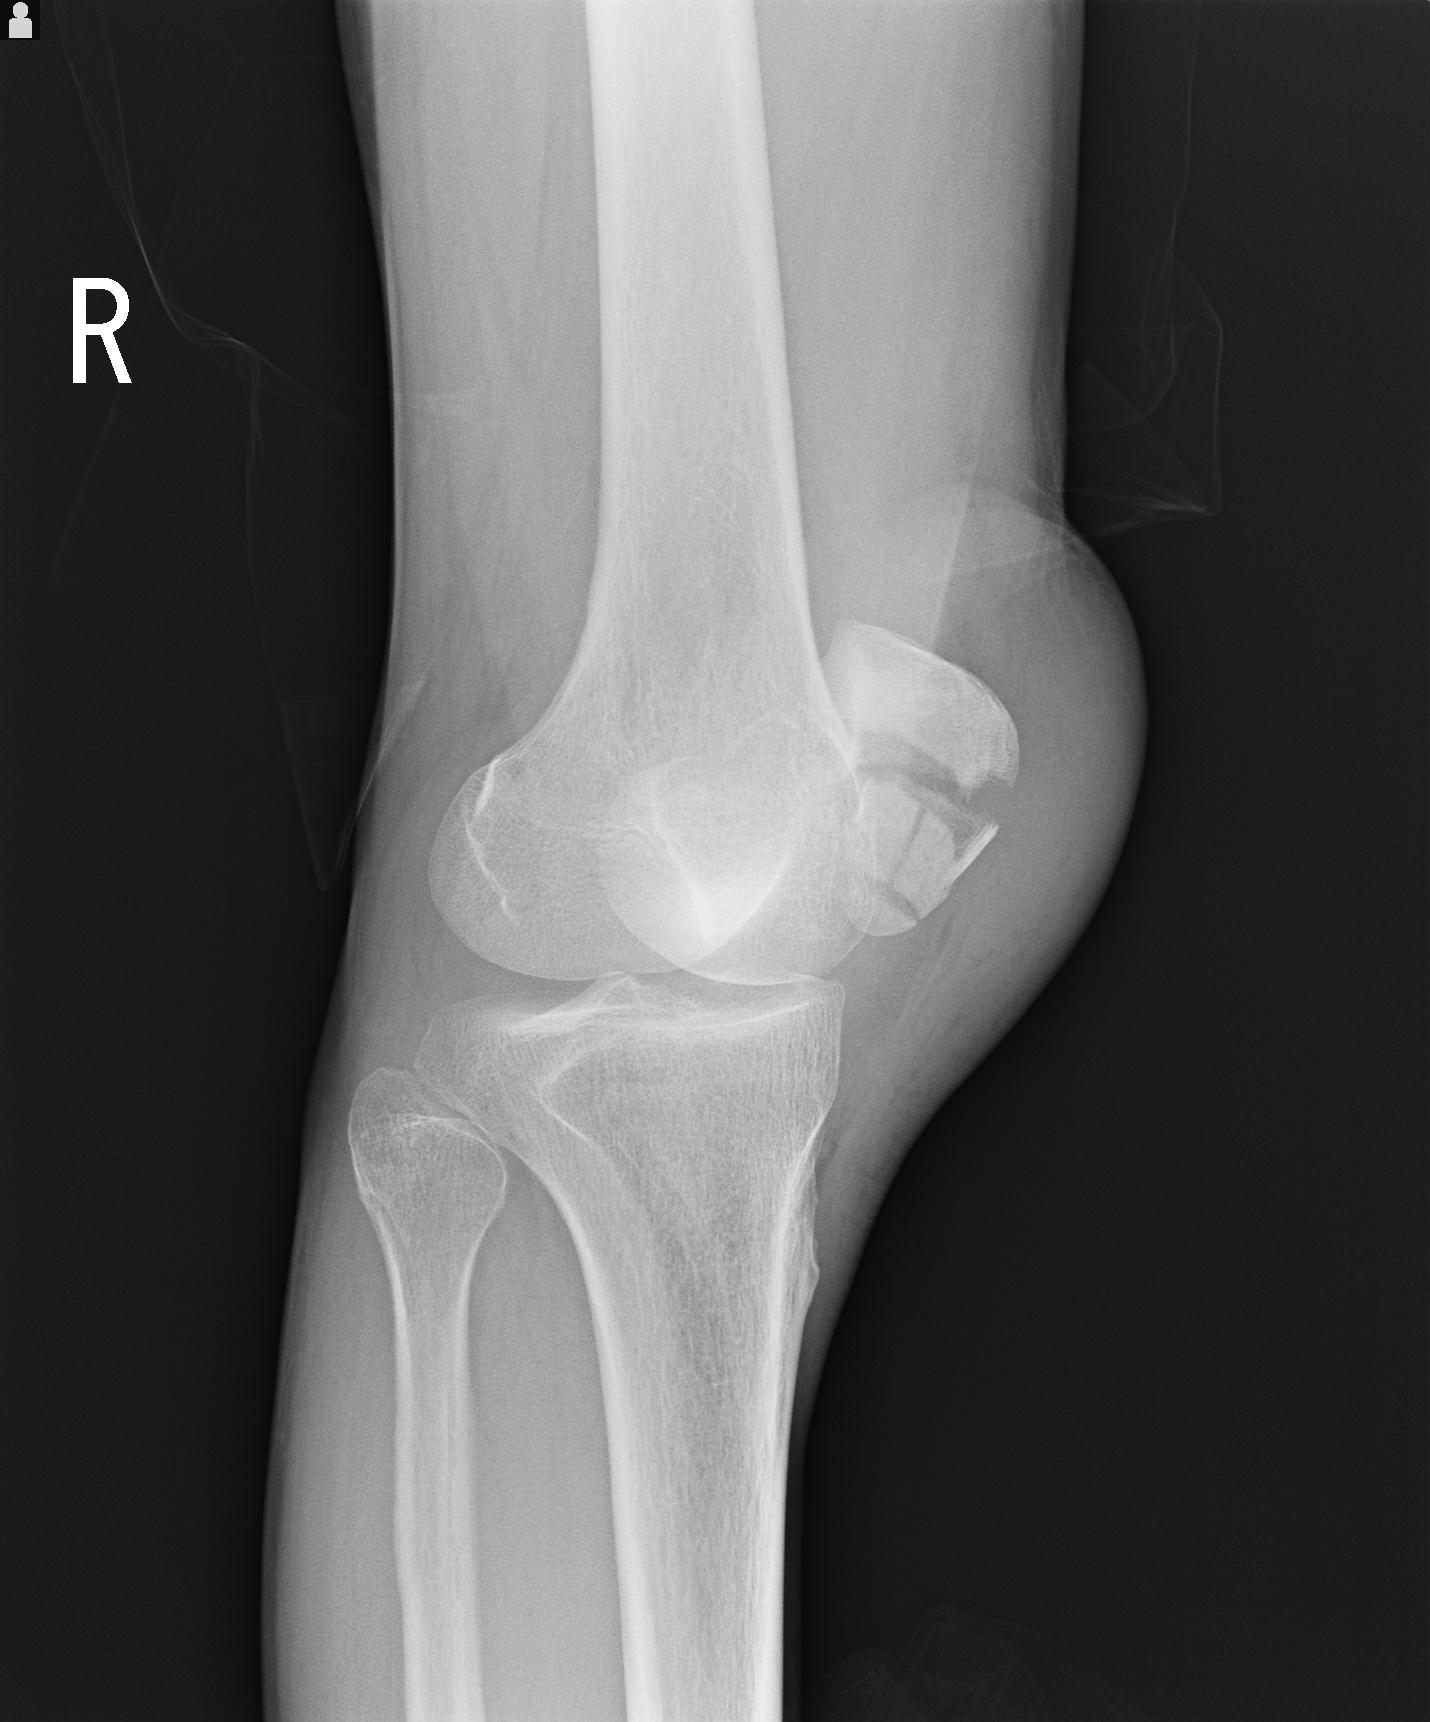

49554 3/13 膝 4R 3/16 4R 1/18 2R 78歳男性 膝蓋骨骨折